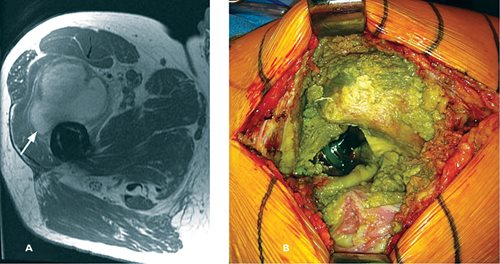

Soft tissue reactions from the metal ions of the MoM bearings are the key issues in failure of the implants and associated complications. The metal ions cause adverse local tissue reactions (ALTRs), osteolysis, enlarged bursae, effusions, creation of pseudotumors, destruction of the abductor muscles, and necrosis. (Fig. 8)

Fig. 8.

A: MARS MRI axial image with pseudotumor (arrow) anterior to the femur and metal-on-metal prosthesis;

B: Intraoperative image of previous metal-on-metal prosthesis causing extensive metallosis and soft tissue destruction.

A lymphocyte dominated immunologic response occurs in the tissue, known as aseptic lymphocyte-dominant vasculitis-associated lesions (ALVAL).

Unfortunately, it is not possible to predict which patients will have these reactions to metal ions. Some patients have symptoms, others have none, but it is generally recommended that even asymptomatic patients should be evaluated yearly with radiographs to assess osteolysis and blood levels of cobalt and chromium ions. Metal ion levels > 7 ppb (parts per billion) are considered elevated, and should instigate advanced imaging. Metal artifact reduction sequence (MARS) MRI helps assess for presence of pseudotumors and integrity of the abductor and gluteal muscles.